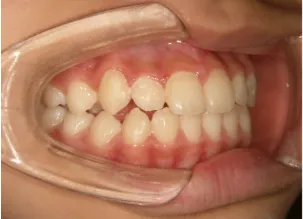

治療中⑦中3:15y5m 口元・咬合の改善で抜歯治療スタート

口元の治療前後:15y5m→17y7m スッキリしました